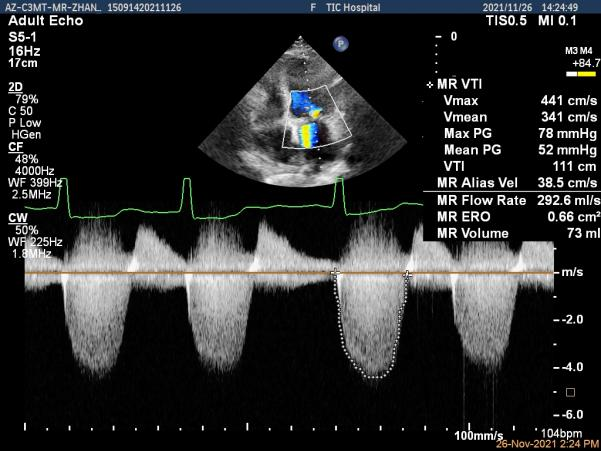

术前超声评估结果

术前超声诊断

Qlab软件勾画估测瓣口面积约:4.42cm²

二尖瓣口平均跨瓣压差:5mmHg